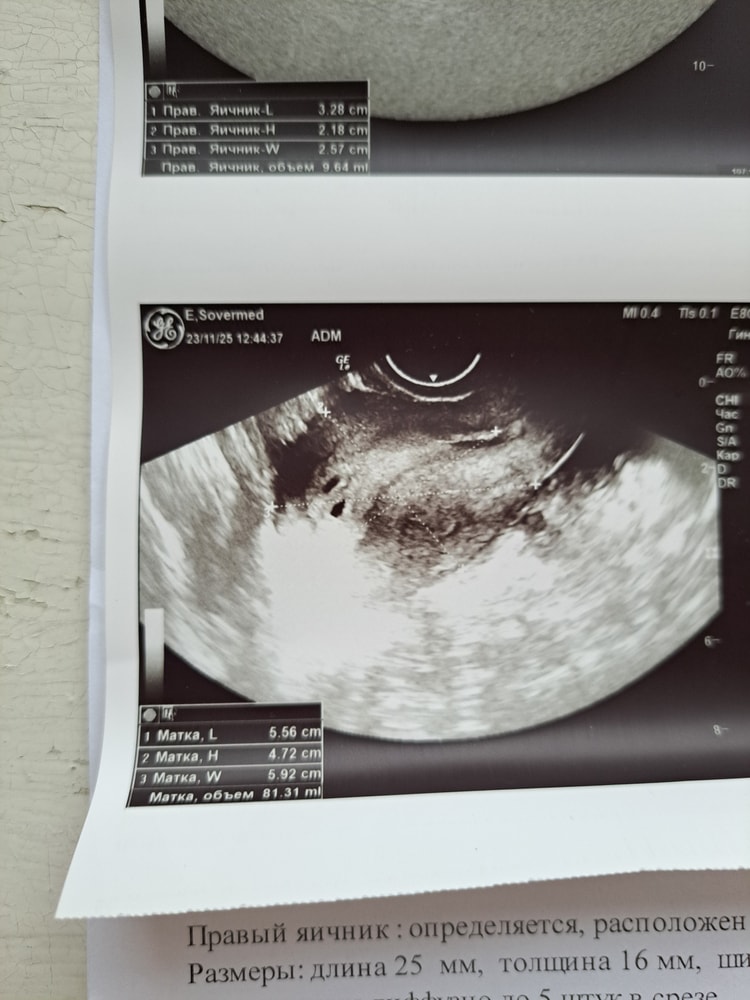

Обследования, узи, анализыДобрый день! Сегодня сходила на узи. (Фото в комментариях) Ровно 5 недель по мес. (Знаю, что рано). Врач на узи увидела 2 плодных яйца, но одно желтое тело 16 мм.

Такое возможно? Очень смущает, что всего 1 желтое тело, хотя в таком случае ведь должно быть 2? Может у кого-то было так-же, что у вас в итоге, 1 или двойня?

Последняя динамика хгч за 48 ч. - 967мМе/мл, затем 3602мМе/мл.